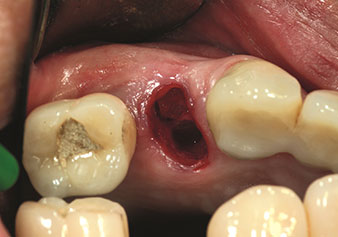

W&H also offers the perfect solution for the internal sinus lift.

Following preparation of the maxillary sinuses with the corresponding instrument set (Fig. 3), the new Z35P instrument (Fig. 4) is used to lift the membrane hydrodynamically. The same instrument set can also be used for piezosurgical preparation of the implant bed in increasing diameters (Figures 3 and 4 included with the kind permission of Dr Mario Kirste, Frankfurt/Oder).